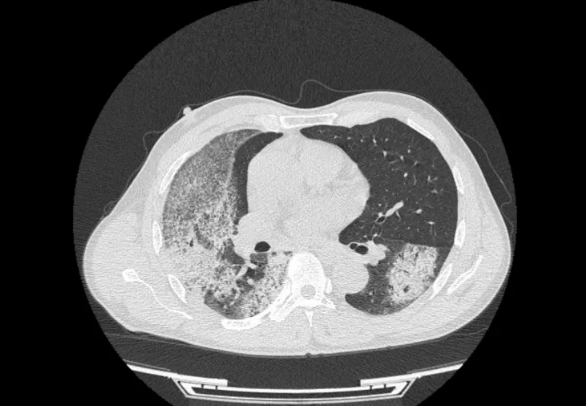

△入院时胸部CT图像

注:图像显示双肺多发渗出病灶,以右肺为著